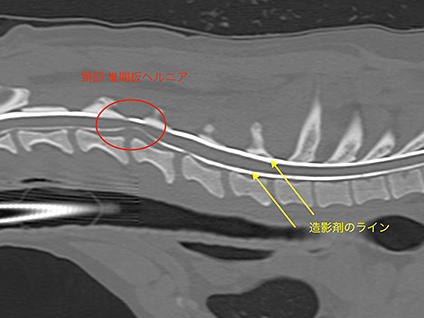

神経疾患におけるCT検査

ミニチュア・ダックスフンドやトイ・プードルなどを始めとして、犬の椎間板ヘルニアや交通事故などでの脊髄の骨折に対し、造影検査や3Dプリンターと組み合わせることで、その治療部位を早期に把握し、同時に手術を行うことができます。